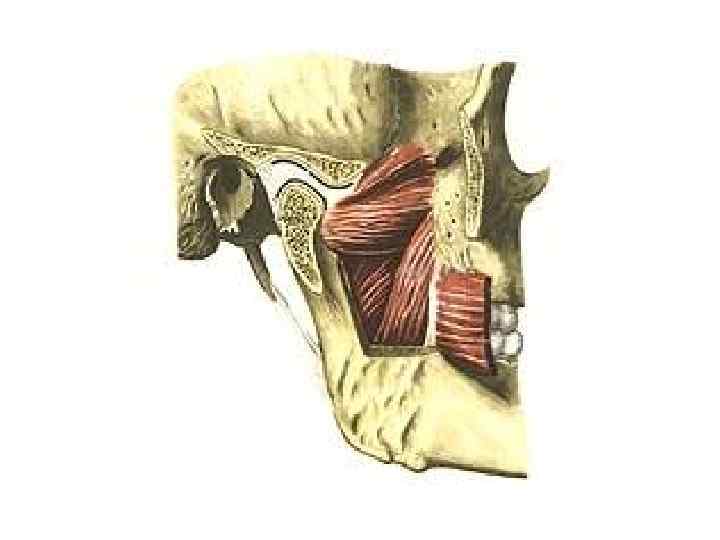

Скронева кістка (os temporale)

Клиноподібна кістка (os sphenoidale)

Клиноподібна кістка (os sphenoidale)

Нижня щелепа (mandibula)